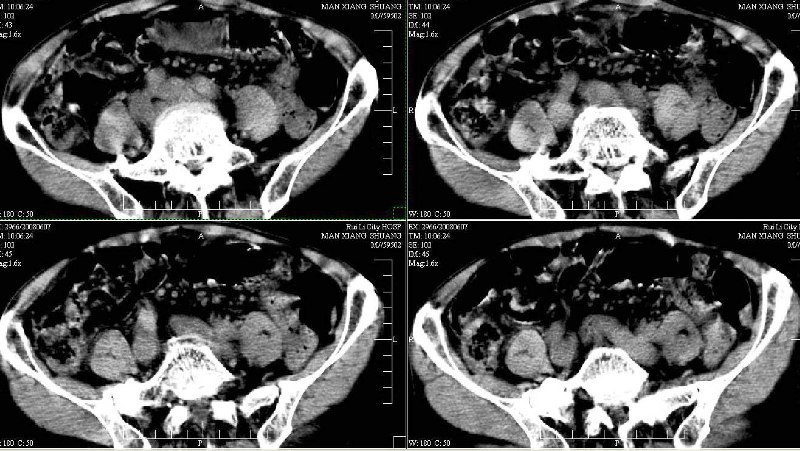

标题: CT13937:M,42A.腰疼一周。 [打印本页]

标题: CT13937:M,42A.腰疼一周。

dr:l4骨质破坏,转移可能。

ct:肝癌腰椎转移。临床医生:肝脏、骨转移,肿瘤来自?前列腺?!

1、支持肝癌肝内及腰椎转移。

2、肝脏内好象有多个病灶,建议增强检查。

3、前列腺好象还可以,不过图像看得不太清。